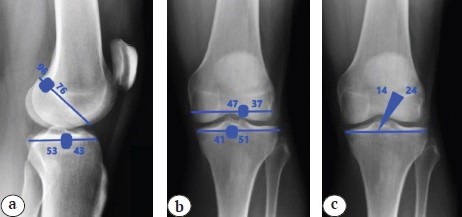

The selected cohort was subjected to radiological examination to differentiate anatomical and nonanatomical ACLR. Plain radiography of both knees in standing anteropasterior view with 0° knee flexion, pasteroanterior view with 30° knee flexion and lateral view with 30° knee flexion were taken. All X-ray images were interpreted in DICOM format in PACS (version 8.2). The anatomical nature of reconstruction was assessed as per the radiological landmarks described by L.A. Pinczewski et al. [9] (Figure 1).

Figure 1. Plain X-rays of the knee joint showing anatomical tunnel parameters and GIA: a — sagittal tunnel positions; b — coronal tunnel positions; c — graft inclination angle

Accordingly, the tunnel parameters analysed in the selected cohort were coronal femoral tunnel position, sagittal femoral tunnel position, coronal tibial tunnel position, sagittal tibial tunnel position and graft inclination angle (GIA). Patients found to have anatomical tunnel position and GIA were then subjected to final analysis (Figure 2). Those who were found to have nonanatomical tunnel position and GIA were excluded from the study.

Figure 2. A patient’s postoperative X-rays showing anatomical tunnel parameters and GIA: a — sagittal tunnel positions; b — coronal tunnel positions; c — graft inclination angle